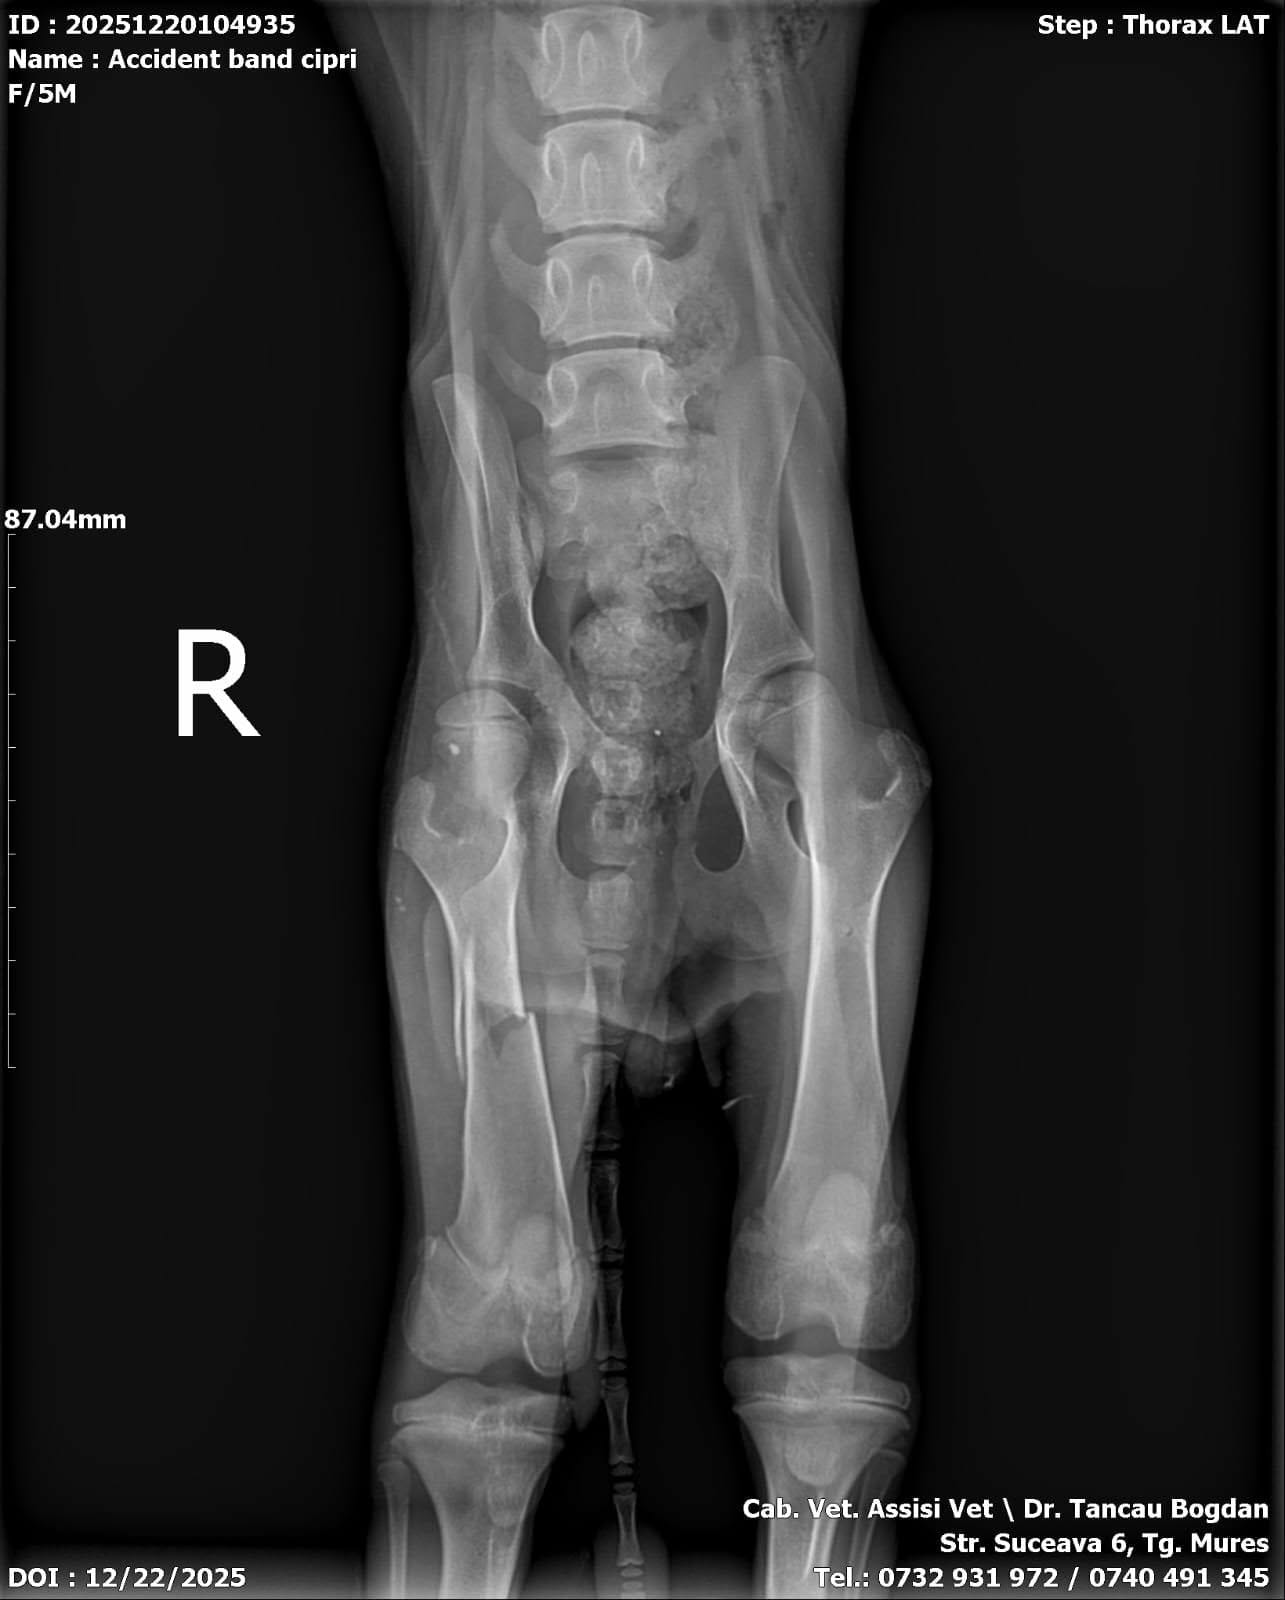

Elena a été trouvée sur une route très fréquentée, où les voitures passent à toute vitesse. Elle était seule, dans un état dévastateur, extrêmement faible, terrorisée, et avec une patte cassée, probablement après avoir été percutée.